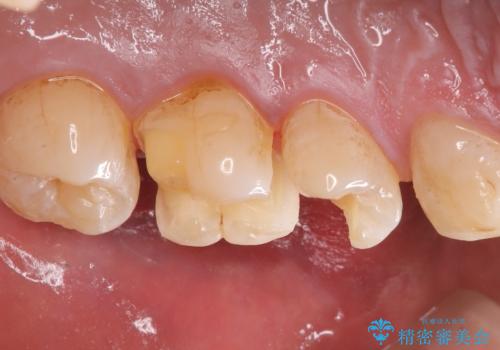

左上5番目の歯の側面に実質欠損を認め、隣の6番目の歯にも虫歯を認めたため両歯ともセラミックインレーでの治療となりました。

左上5番遠心に実質欠損を認め、さらに5番と6番の隣接面にもカリエスを認めました。6番の咬合面には、元々コンポジットレジン修復が施されており、劣化がみられたのでその部分も含め修復することとなりました。